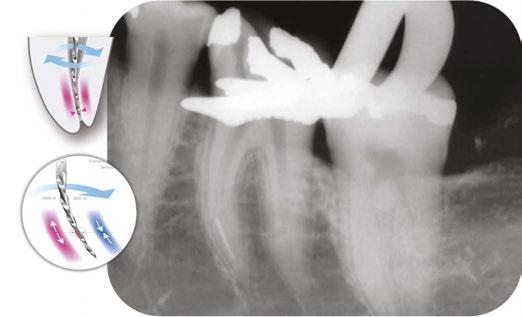

Drs. Carlos A. Spironelli Ramos and Ken Serota discuss the heat-treatment manufacturing process

The adoption of advanced rotary file systems, such as those with variable tapers, e.g., the DC Taper file system from SS White Dental, is a prime example of refined instrumentation. These designs intelligently adapt to the natural canal anatomy from coronal to apical, reducing unnecessary dentin removal and significantly minimizing stress on areas prone to fracture. This ensures both effective cleaning and superior tooth preservation.